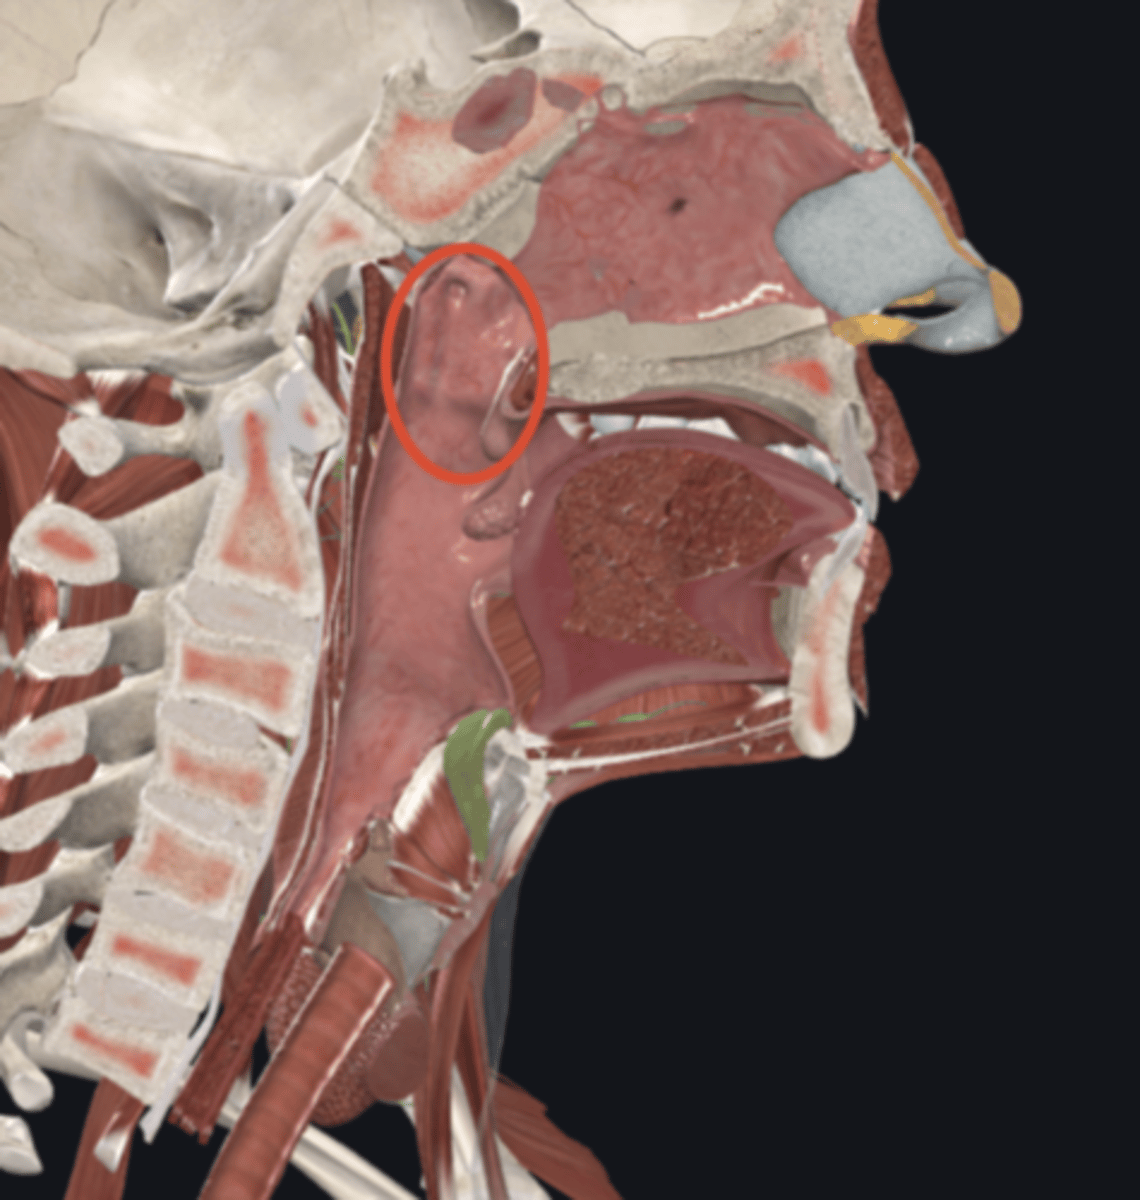

nasopharynx

name the circled region

oropharynx

name the circled region

laryngopharynx

name the circled region